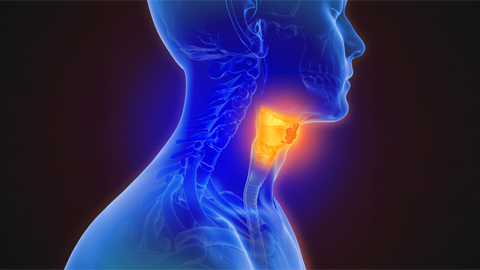

Pan-kinase inhibitor for head and neck cancer enters clinical trials

A drug targeting the scaffolding function of multiple related kinases halts tumor progression.